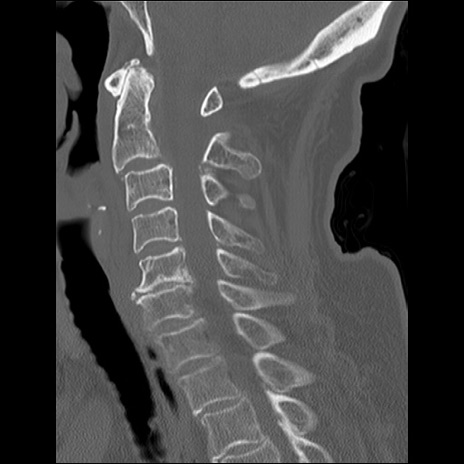

冠状断像